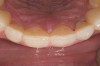

Figure 18  1:1 view of restored palatal surfaces with nanofilled resin.

Table 1

White enamel shade was placed on the putty index and carried to the palatal surface of No. 9. This layer was spread uniformly and thinned out and spread along the entire width of the tooth (Figure 11). After curing this layer, A2 dentin was layered to simulate the lobular pattern seen in dentin of the natural teeth (Figure 12). After curing, a layer of transparent resin was placed in the incisal areas between the dentinal lobes. The final layer of A2 enamel was built and shaped to full contour (Figure 13). A similar build-up was done for all the remaining anterior teeth. The bite in MIP was adjusted such that there was uniform contact on all anterior teeth. The anterior guidance was harmonized to maintain uniformity in the contact of the incisors during protrusion and the canines and incisors during lateral excursions. Finishing and polishing was done per protocol (Figure 14 through Figure 18).13

The patient was recalled at frequent intervals, and after 8 months, occlusal equilibration was done to harmonize the discrepancy between MIP and CR and to have uniform, stable holding contacts on all posterior teeth and re-confirm that the anterior guidance was adequate to disclude posteriors.